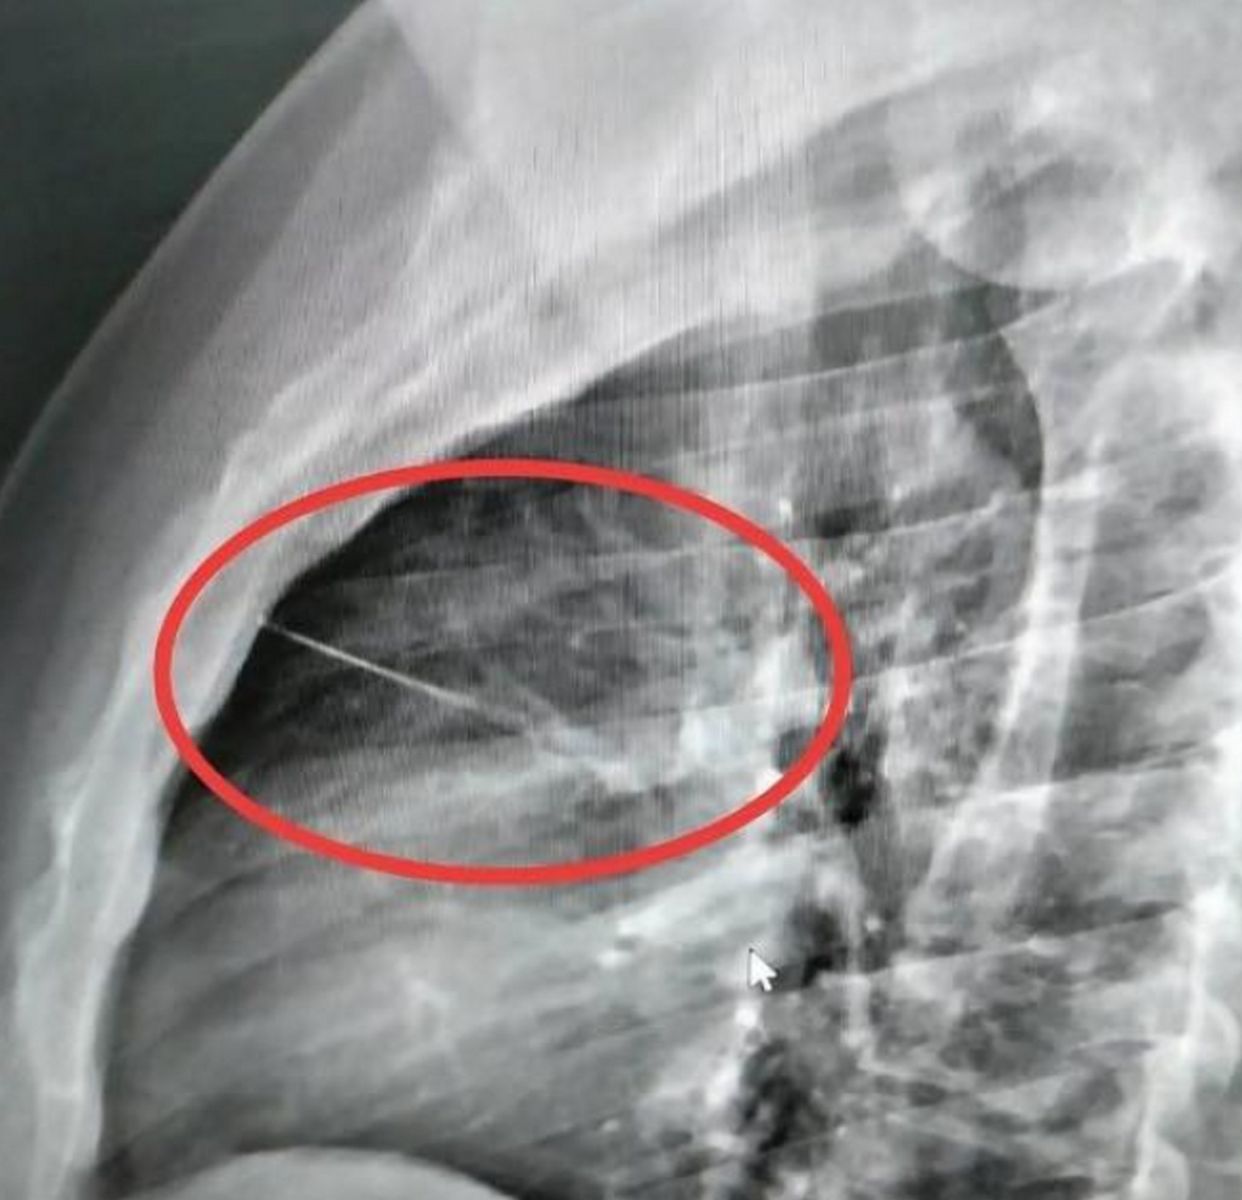

เมื่อไปถึงโรงพยาบาลอาการ ก็ยังไม่ดีขึ้นหมอจึงนำตัวไปเอ็กซ์เรย์ ปรากฏว่ามีวัตถุคล้ายของมีคมขนาดเล็กความยาวประมาณ 7 ซม.ทราบต่อมาว่าเป็นเข็มเย็บผ้า ฝังอยู่บริเวณหน้าอกซ้ายใกล้กับหัวใจ แพทย์จึงส่งตัวไปผ่าตัดที่โรงพยาบาลศูนย์บุรีรัมย์ เพราะเป็นจุดอันตราย

ขณะที่หลานคนเจ็บเล่าว่า ตอนนี้แพทย์แจ้งว่าอาการสาหัสจะต้องทำการผ่าตัด เบื้องต้นพบว่าเป็นเข็มเย็บผ้าที่น้าชายลืมไว้เองบนที่นอนและคาดว่าจะเหนื่อยจากการทำงานแล้วล้มตัวนอนบนที่นอนแล้วไปโดนเข็มแทงหน้าอกดังกล่าว